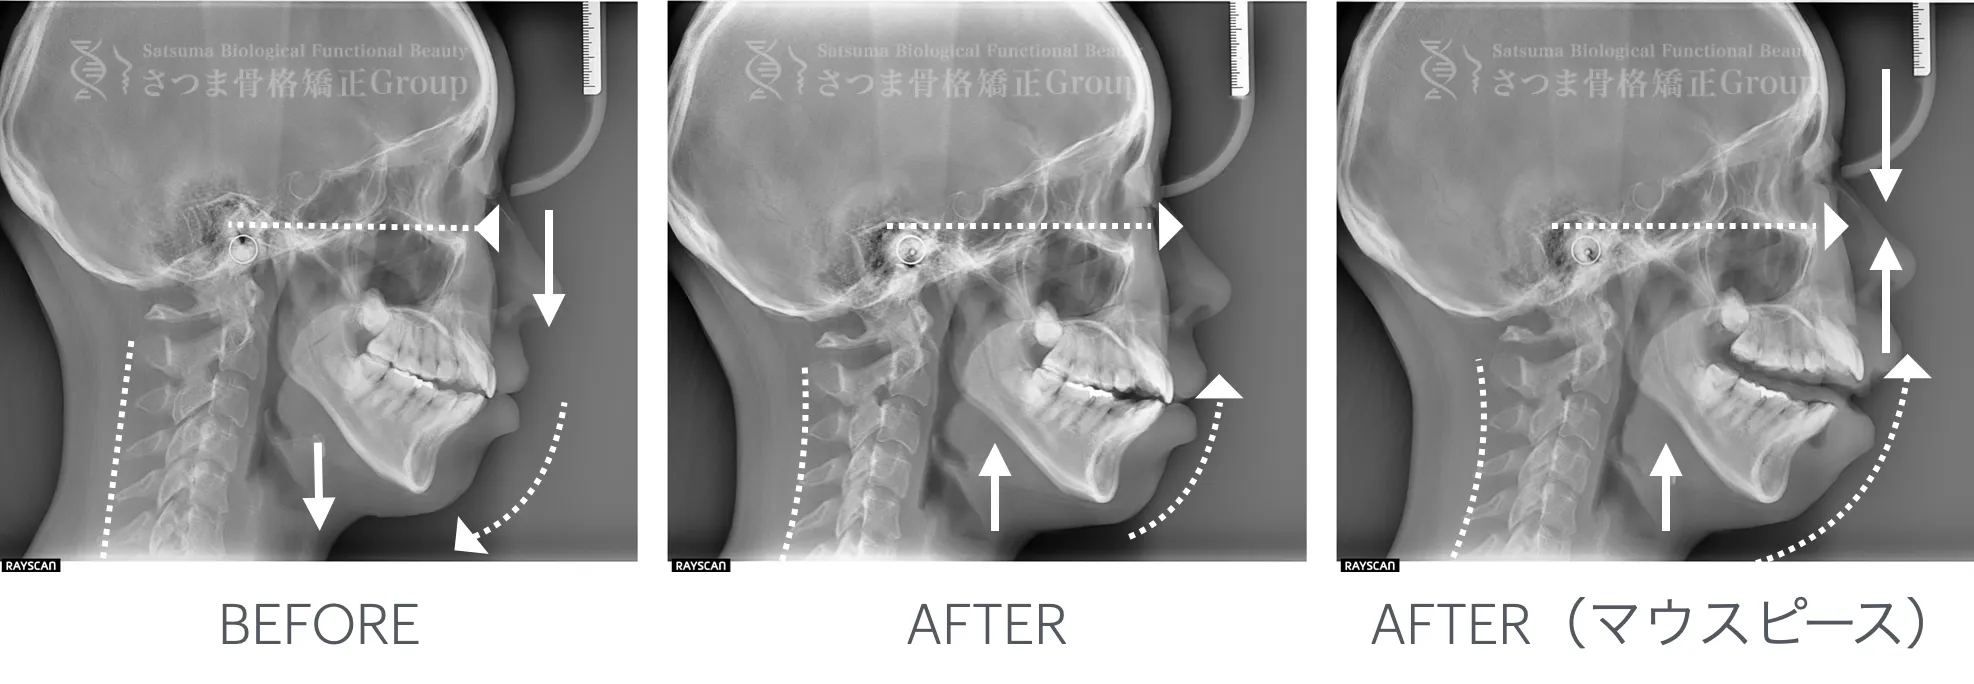

最新のCTスキャンによる顎・顔面・頚椎の立体画像検査を導入。

治療前後の変化を視覚的に確認できるため、

改善のプロセスを“見てわかる”形で効果を実感いただけます。